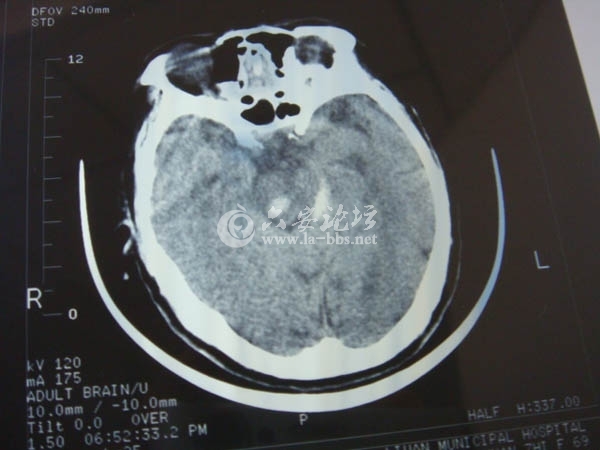

2012年11月21号晚一辆无牌照摩托车撞到一同向行走老人,送至医院检查为脑干出血(希望有医疗专家看到此贴可以跟帖帮忙出注意,看有什么好的方法救治病人,谢谢),院方当晚就已下达病危通知书,(事发安徽省

市三十铺镇松林村村部附近)受害者至今未醒。